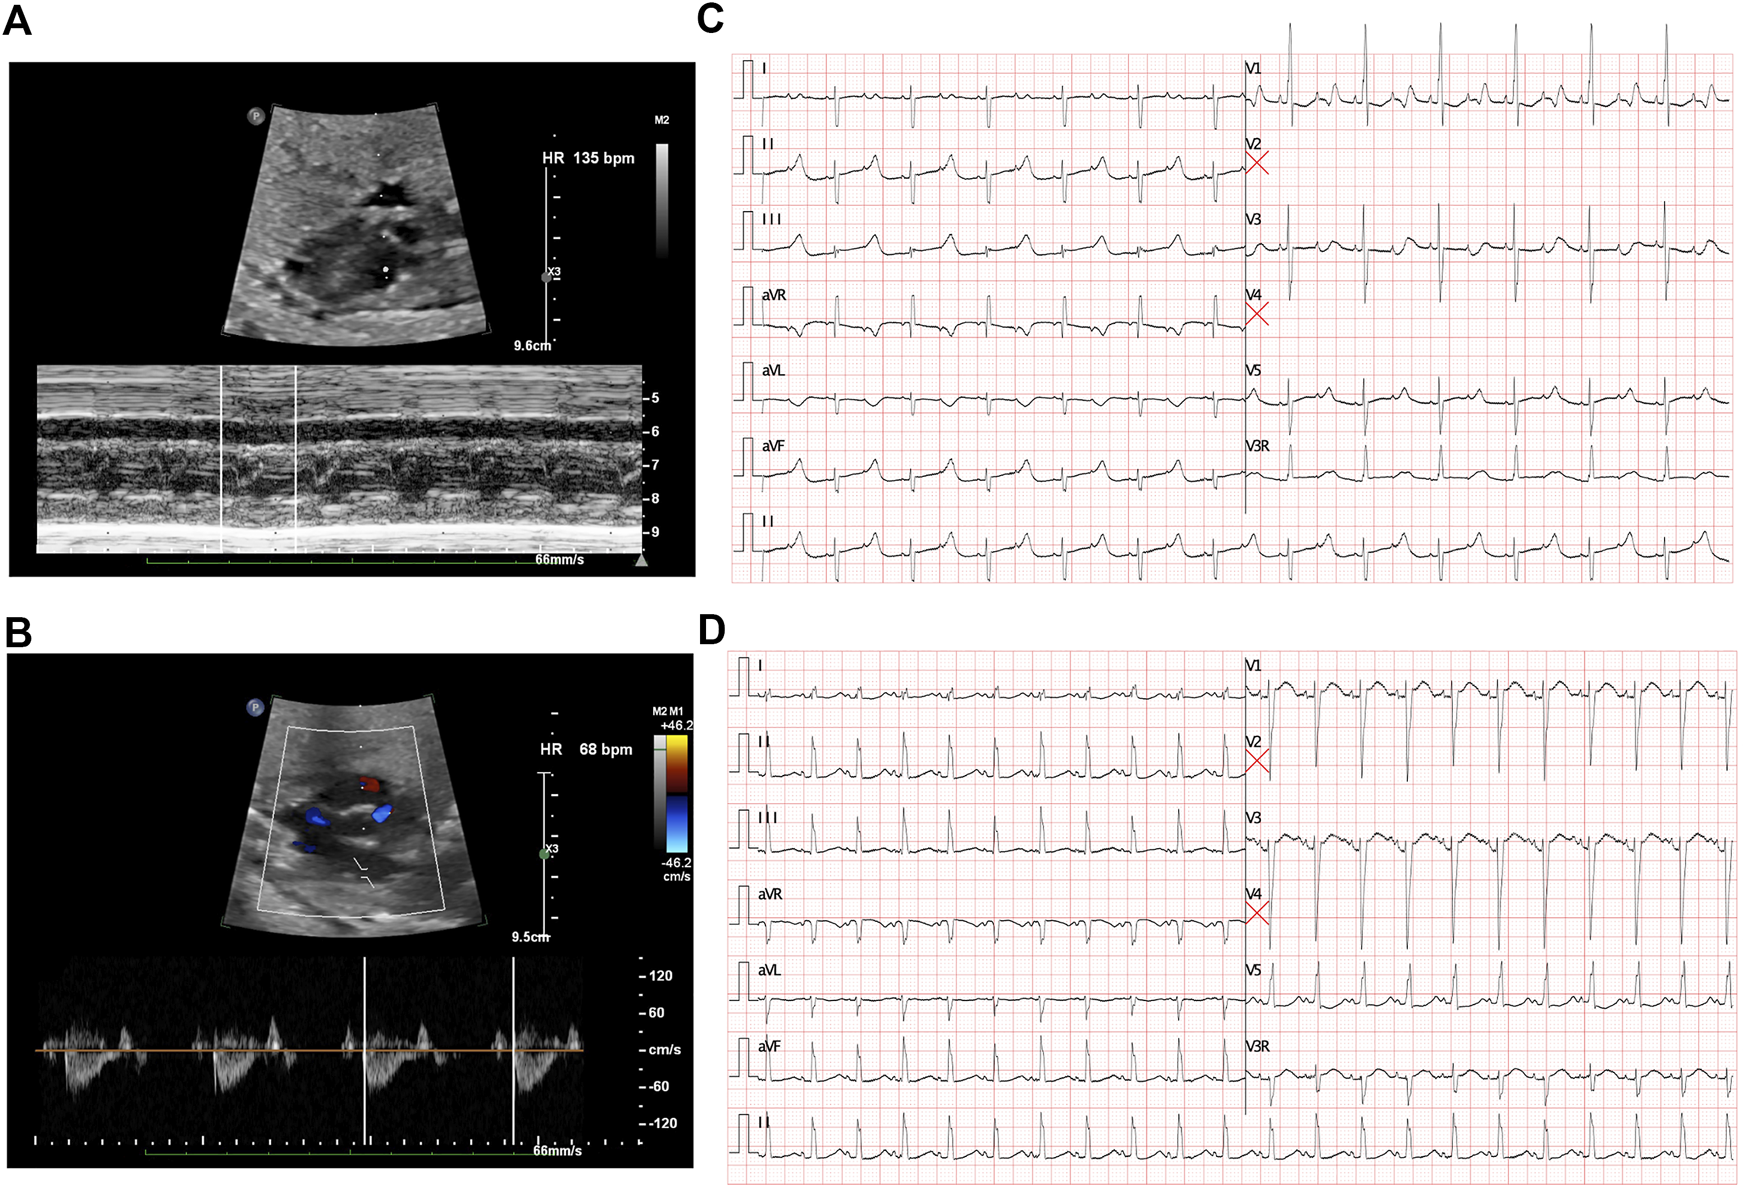

The first intrapartum fetal echocardiography exam was performed at 28 + 2 gestational weeks, and the development of the four cardiac chambers and valvar movements were normal. The atrial rate was 135 beats/min, while the ventricular rate was 68 beats/min (Figures 1A and B), and the cardiovascular system profile was normal (10/10 points). Thus, a diagnosis of fetal AVB (second degree, type II) was identified. The maternal autoimmune antibody test results were negative for anti–Ro/SSA (0.8 RU/mL, n.v. < 20 RU/mL), anti–La/SSB (<0.5 RU/mL, n.v. < 20 RU/mL), and ANAs (negative, n.v. < 1:100). The IgM result for adenovirus, coxsackie virus, and B-19 were all negative. Next, DEX (4.5 mg/day) was provided to the mother. During fetal follow-up at 34 + 3 gestational weeks, a fetal AVB of 2:1 transduction changed into a first-degree AVB with a prolonged AV interval (147 ms) as the ventricular rate was 130–142 beats/min and the cardiovascular system profile remained normal. Thus, the DEX treatment seemed to confer some benefits in this case. At this point, the dosage of DEX was reduced to 1.5 mg/day until delivery.

FIGURE 1

Fetal echocardiography to determine bradycardia. (A) M-mode echocardiography demonstrated an atrial rate of 135 beats per minute before treatment. (B) Doppler demonstrated a ventricular rate of 68 beats per minute before treatment and indicated a 2:1 AV block. (C) ECG presented a 2:1 transduction atrioventricular block postnatally. (D) ECG revealed a significant prolonged QTc interval after birth.